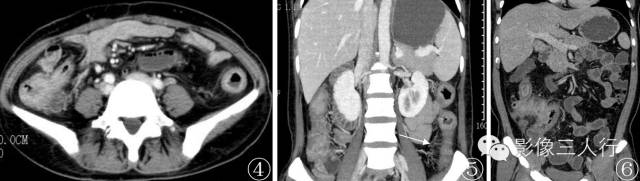

图 4 , 5 女 , 41 岁 。 Crohn 病 。 回肠末端及结肠全程肠壁增厚 ,分层强化 ,降结肠系膜血管增多(梳征 )

图 6 男 , 36 岁 。 Crohn 病 。 回肠末段及升结肠肠壁增厚 、粘连 ,肠腔狭窄 ,升结肠分层状强化